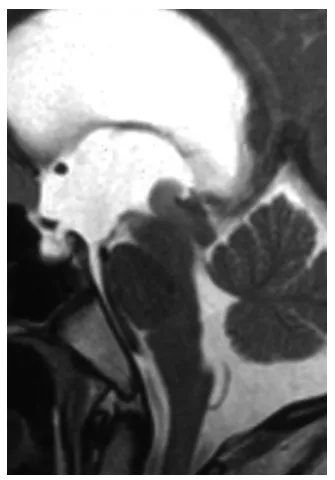

脑干脑桥海绵状血管瘤一旦出血,后果不堪设想。手术切除是根治病灶的希望所在。然而,手术风险极高,稍有不慎便可能伤及重要神经,如何选择最安全的手术入路,是神经外科领域持续探索...